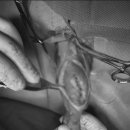

• 24시 에피소드 동물 메디컬 센터 | 만촌동 동물병원 강아지 요골·척골 골절 수술 후기 [24시에피소드동물메디컬센터]

만촌동 동물병원 강아지 요골·척골 골절 수술 후기 [24시에피소드동물메디컬센터] 만촌동 동물병원 ​ 안녕하세요. ​ 풍부한 경험과 따듯한 진료를 바탕으로, 반려동물의 건강하고 행복한 하루하루를 함께 만들어 가는 만촌동 동물병원 24시에피소드동물메디컬센터 입니다. 24시에피소드동물메디컬센터 대구광역시 동구...

에피소드동물메디컬센터(2025-06-26 12:41:00)